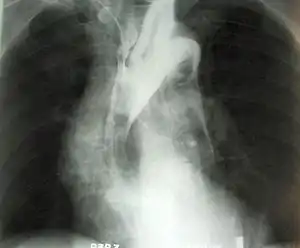

Anevrismul reprezintă o formațiune vasculară cu aspect tumoral, localizată pe traiectul unei artere (cel mai des) sau vene[1]. Se prezintă ca o dilatare (ca un sac) a vasului sanguin și poate fi localizat oriunde în organism[2]. Cu toate acestea, cel mai adesea el se dezvoltă în segmentul abdominal al arterei aortice și la nivelul vaselor creierului (anevrism cerebral)[3]. În majoritatea cazurilor este asimptomatic.

Termenul se mai folosește – în cadrul unor cuvinte compuse, pentru o descrie condiția în care apare o dilatație patologică segmentară situată la nivelul peretelui inimii – cel mai frecvent situată la nivelul ventriculului stîng și adesea consecința unui infarct miocardic transmural.[4]